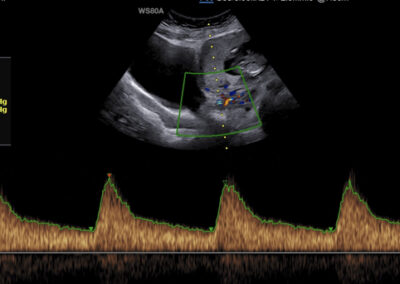

Specialized scans

Genetic ultrasound Fetal echocardiography Doppler assesment of feto-placental circulation Screening for preterm delivery Screening for pre-eclampsia and fetal growth restriction Multiple pregnancy 3D-4D scan Gender scan